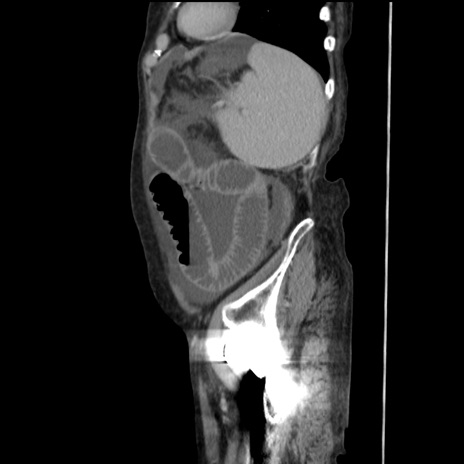

横断像

【症例】80歳代 女性

【主訴】腹部膨満感

【現病歴】他院にて肝硬変にてフォロー中。1週間前から便秘、腹部膨満感、臍部腫瘤あり受診となる。

【既往歴】肝硬変

【身体所見】腹部膨隆あり、皮膚変化なし、疼痛なし。

【データ】WBC 4600、CRP 0.25